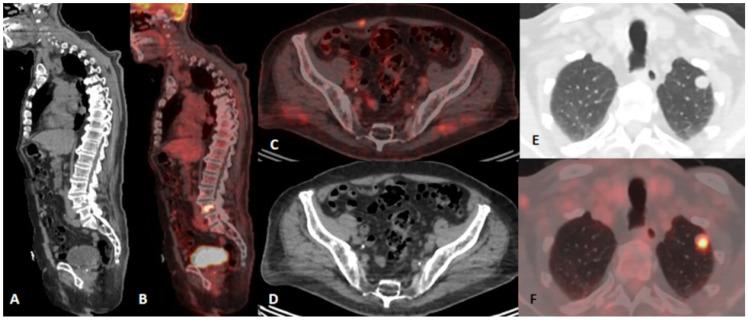

The global increase in the incidence of malignant melanoma, without significant changes in the mortality rate, may be influenced by the changes in the diagnostic approach and criteria, and the impact of innovative therapies on the survival of patients. Advances in treatment options, influencing prolonged survival, are bringing up a strong need for close surveillance of melanoma patients. In this observational, retrospective, and single-center study, we determined the impact of 18F-FDG PET/CT diagnostics on the outcomes and survival of malignant melanoma patients at different stages from an extensive and unselected group in a real-life clinical management setting. A total number of 189 malignant melanoma patients who underwent 18F-FDG PET/CT examination in the course of the treatment at one university oncology institute during the period from January 2010 to December 2024 were included in the study, and the multifactorial impact on the outcome and survival of malignant melanoma patients was observed in regard to the differences resulting from the therapeutic approaches and the introduction of new therapeutic options and drugs. Our results indicate that 18F-FDG PET/CT is a sensitive imaging tool for the detection of predominantly distant metastases in malignant melanoma patients belonging to an extensive and unselected population in a real-world clinical setting, not only at advanced melanoma stages but also at early stages of high-risk patients' surveillance. Follow-up appears to be of substantial importance for patients at advanced stages, but also for patients at early stages of disease, in particular in the presence of a strong clinical suspicion. Immunotherapy and combined therapy are improving overall survival in melanoma patients in real-world circumstances and equivalent clinical surroundings.

全球恶性黑色素瘤发病率上升,但死亡率无显著变化,这可能受到诊断方法和标准的改变以及创新疗法对患者生存影响的影响。治疗选择的进步延长了患者生存期,这使得对黑色素瘤患者进行密切监测的需求日益强烈。在这项观察性、回顾性单中心研究中,我们在真实临床管理环境下,从一个广泛且未经过筛选的群体中,确定了18F-FDG PET/CT诊断对不同阶段恶性黑色素瘤患者的治疗结果和生存情况的影响。本研究纳入了2010年1月至2024年12月期间在一所大学肿瘤研究所接受治疗过程中进行18F-FDG PET/CT检查的189例恶性黑色素瘤患者,并观察了治疗方法以及新治疗方案和药物的引入所导致的差异对恶性黑色素瘤患者治疗结果和生存情况的多因素影响。我们的结果表明,18F-FDG PET/CT是一种敏感的成像工具,不仅在晚期黑色素瘤阶段,而且在高危患者早期监测阶段,都能在真实临床环境中检测出广泛且未经过筛选人群中恶性黑色素瘤患者的主要远处转移。随访对于晚期患者以及疾病早期患者似乎都至关重要,特别是在临床高度怀疑的情况下。在真实世界和等效临床环境中,免疫疗法和联合疗法正在改善黑色素瘤患者的总生存期。